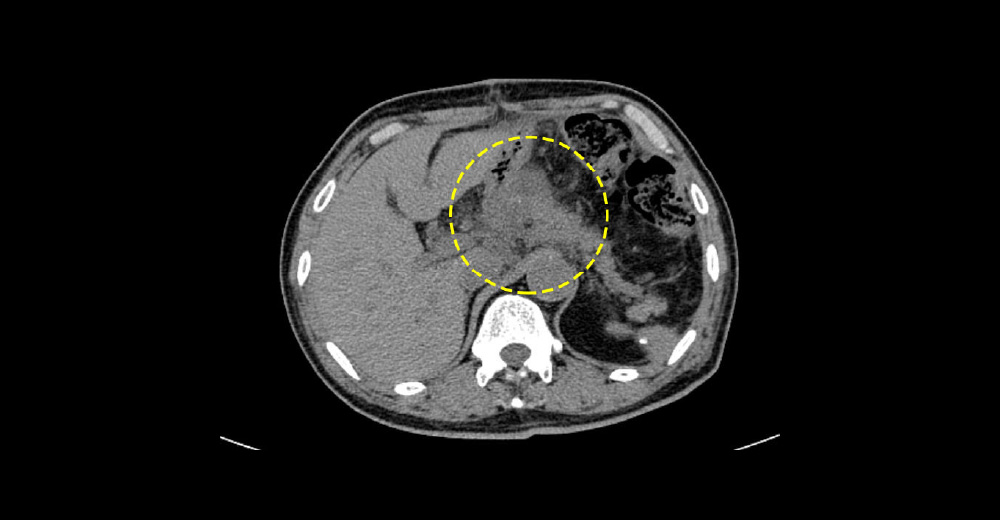

虚血性腸炎

糖尿病や高血圧、喫煙などによる動脈効果の結果、大腸粘膜の血流が減少して、粘膜の炎症が起こり、腹痛や下血を契機に診断されます。下行結腸やS状結腸に好発し、内視鏡では、腸管の縦方向にびらんや潰瘍ができます。

虚血性腸炎 虚血性腸炎